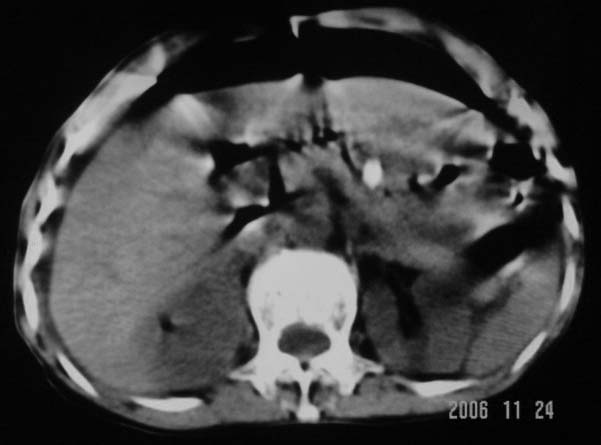

仰卧位见:肝前间隙及肝脾间隙内可见新月形气体密度影,边缘清楚,侧卧位见气体随体位改变而移动,ct值约-929hu。膈下、肝下间隙及部分肠间隙可见液性密度影。考虑:1、上腹部空腔脏器穿孔,以胃穿孔可能性大。2、少量腹水。

仰卧位见:肝前间隙及肝脾间隙内可见新月形气体密度影,边缘清楚,侧卧位见气体随体位改变而移动,ct值约-929hu。膈下、肝下间隙及部分肠间隙可见液性密度影。考虑:1、上腹部空腔脏器穿孔,结合临床,首先考虑胃穿孔可能性大。2、少量腹水

补充--肝门及肝肾间隙以见积气显示。

支持消化道空腔脏器穿孔(腹腔内大量游离气体影,小网膜囊内亦见气体影),少量腹水。